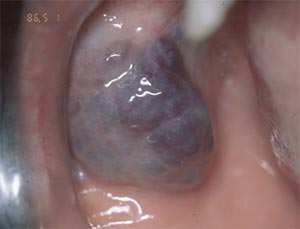

Fueron seleccionados 20 pacientes niños, niñas y adolescentes provenientes del Servicio de Patología y Clínica Estomatología de la Facultad de Odontología de la Universidad Central de Venezuela, entre el período de Octubre de 2002 hasta Julio del 2005, de ambos sexos y en edades comprendidas entre 1 y 16 años respectivamente, con diagnóstico clínico de hemangiomas localizados a nivel de los tejidos blandos de la cavidad bucal; para lo cual se les realizó la prueba clínica de la Vitro presión ó diascopia. (Fig.1)

Fig 1

Vitro presión

Fuete Propio